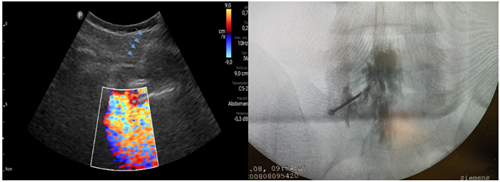

Los procedimientos fueron realizados en sala de operaciones, con vía venosa periférica y en posición decúbito ventral. Los mismos fueron realizados por el investigador principal (P. C.) con experiencia en la realización de procedimientos ecoguiados en la columna vertebral, utilizando la técnica paramediana en eje ecográfico corto. Se utilizó un ecógrafo portátil modelo Lumify marca Phillips, con transductor curvo de baja frecuencia. Fundas y gel ecográfico de la marca Pajunk® (Pajunk GmbH Medizintechnologie, Geisingen, Germany). En cada caso se identificó el espacio L4-L5 o L5-S1 mediante escaneo ecográfico de la columna lumbosacra en el plano transversal y longitudinal previo al inicio del procedimiento. Con la sonda ecográfica colocada en plano transversal o en eje corto, se realiza un habón anestésico 1 a 2 cm a un lado del transductor, correspondiente al lado del dolor radicular. La aguja de Tuohy ecogénica, 18 G (Tuohy Sono, 18G Pajunk® GmbH Medizintechnologie, Geisingen, Germany) de 9 o 12 cm según la contextura del paciente, se dirige en plano, en tiempo real, en sentido lateral a medial, entre la articulación facetaria por fuera y el ligamento interespinoso por dentro, hasta alcanzar el ligamento amarillo, en el espacio interlaminar elegido (Figura 1). El espacio epidural fue identificado mediante la pérdida de resistencia con suero fisiológico. Se registró la imagen doppler color durante la maniobra, como medida alternativa a la epidurografía con contraste (Figura 2). Posteriormente, 5 cc de contraste no iónico fue inyectado. Se consideró que fue alcanzado dicho espacio cuando el contraste se distribuye a lo largo del ligamento longitudinal posterior (Figura 2). 1 mg/kg de triamcinolona más 3 cc de lidocaína al 0,5 (hasta 10 cc de solución total) se inyectan en el espacio epidural.

Fig. 2. Inyección de 5 a 10 ml de suero fisiológico con registro de la imagen doppler color, que se distribuye en el canal raquídeo, en una inyección epidural L5S1 paramediana derecha (imagen a la izquierda). Las flechas azules indican el trayecto de la aguja de Touhy. A la derecha se observa la confirmación con epidurograma de una inyección epidural L5S1 izquierda.